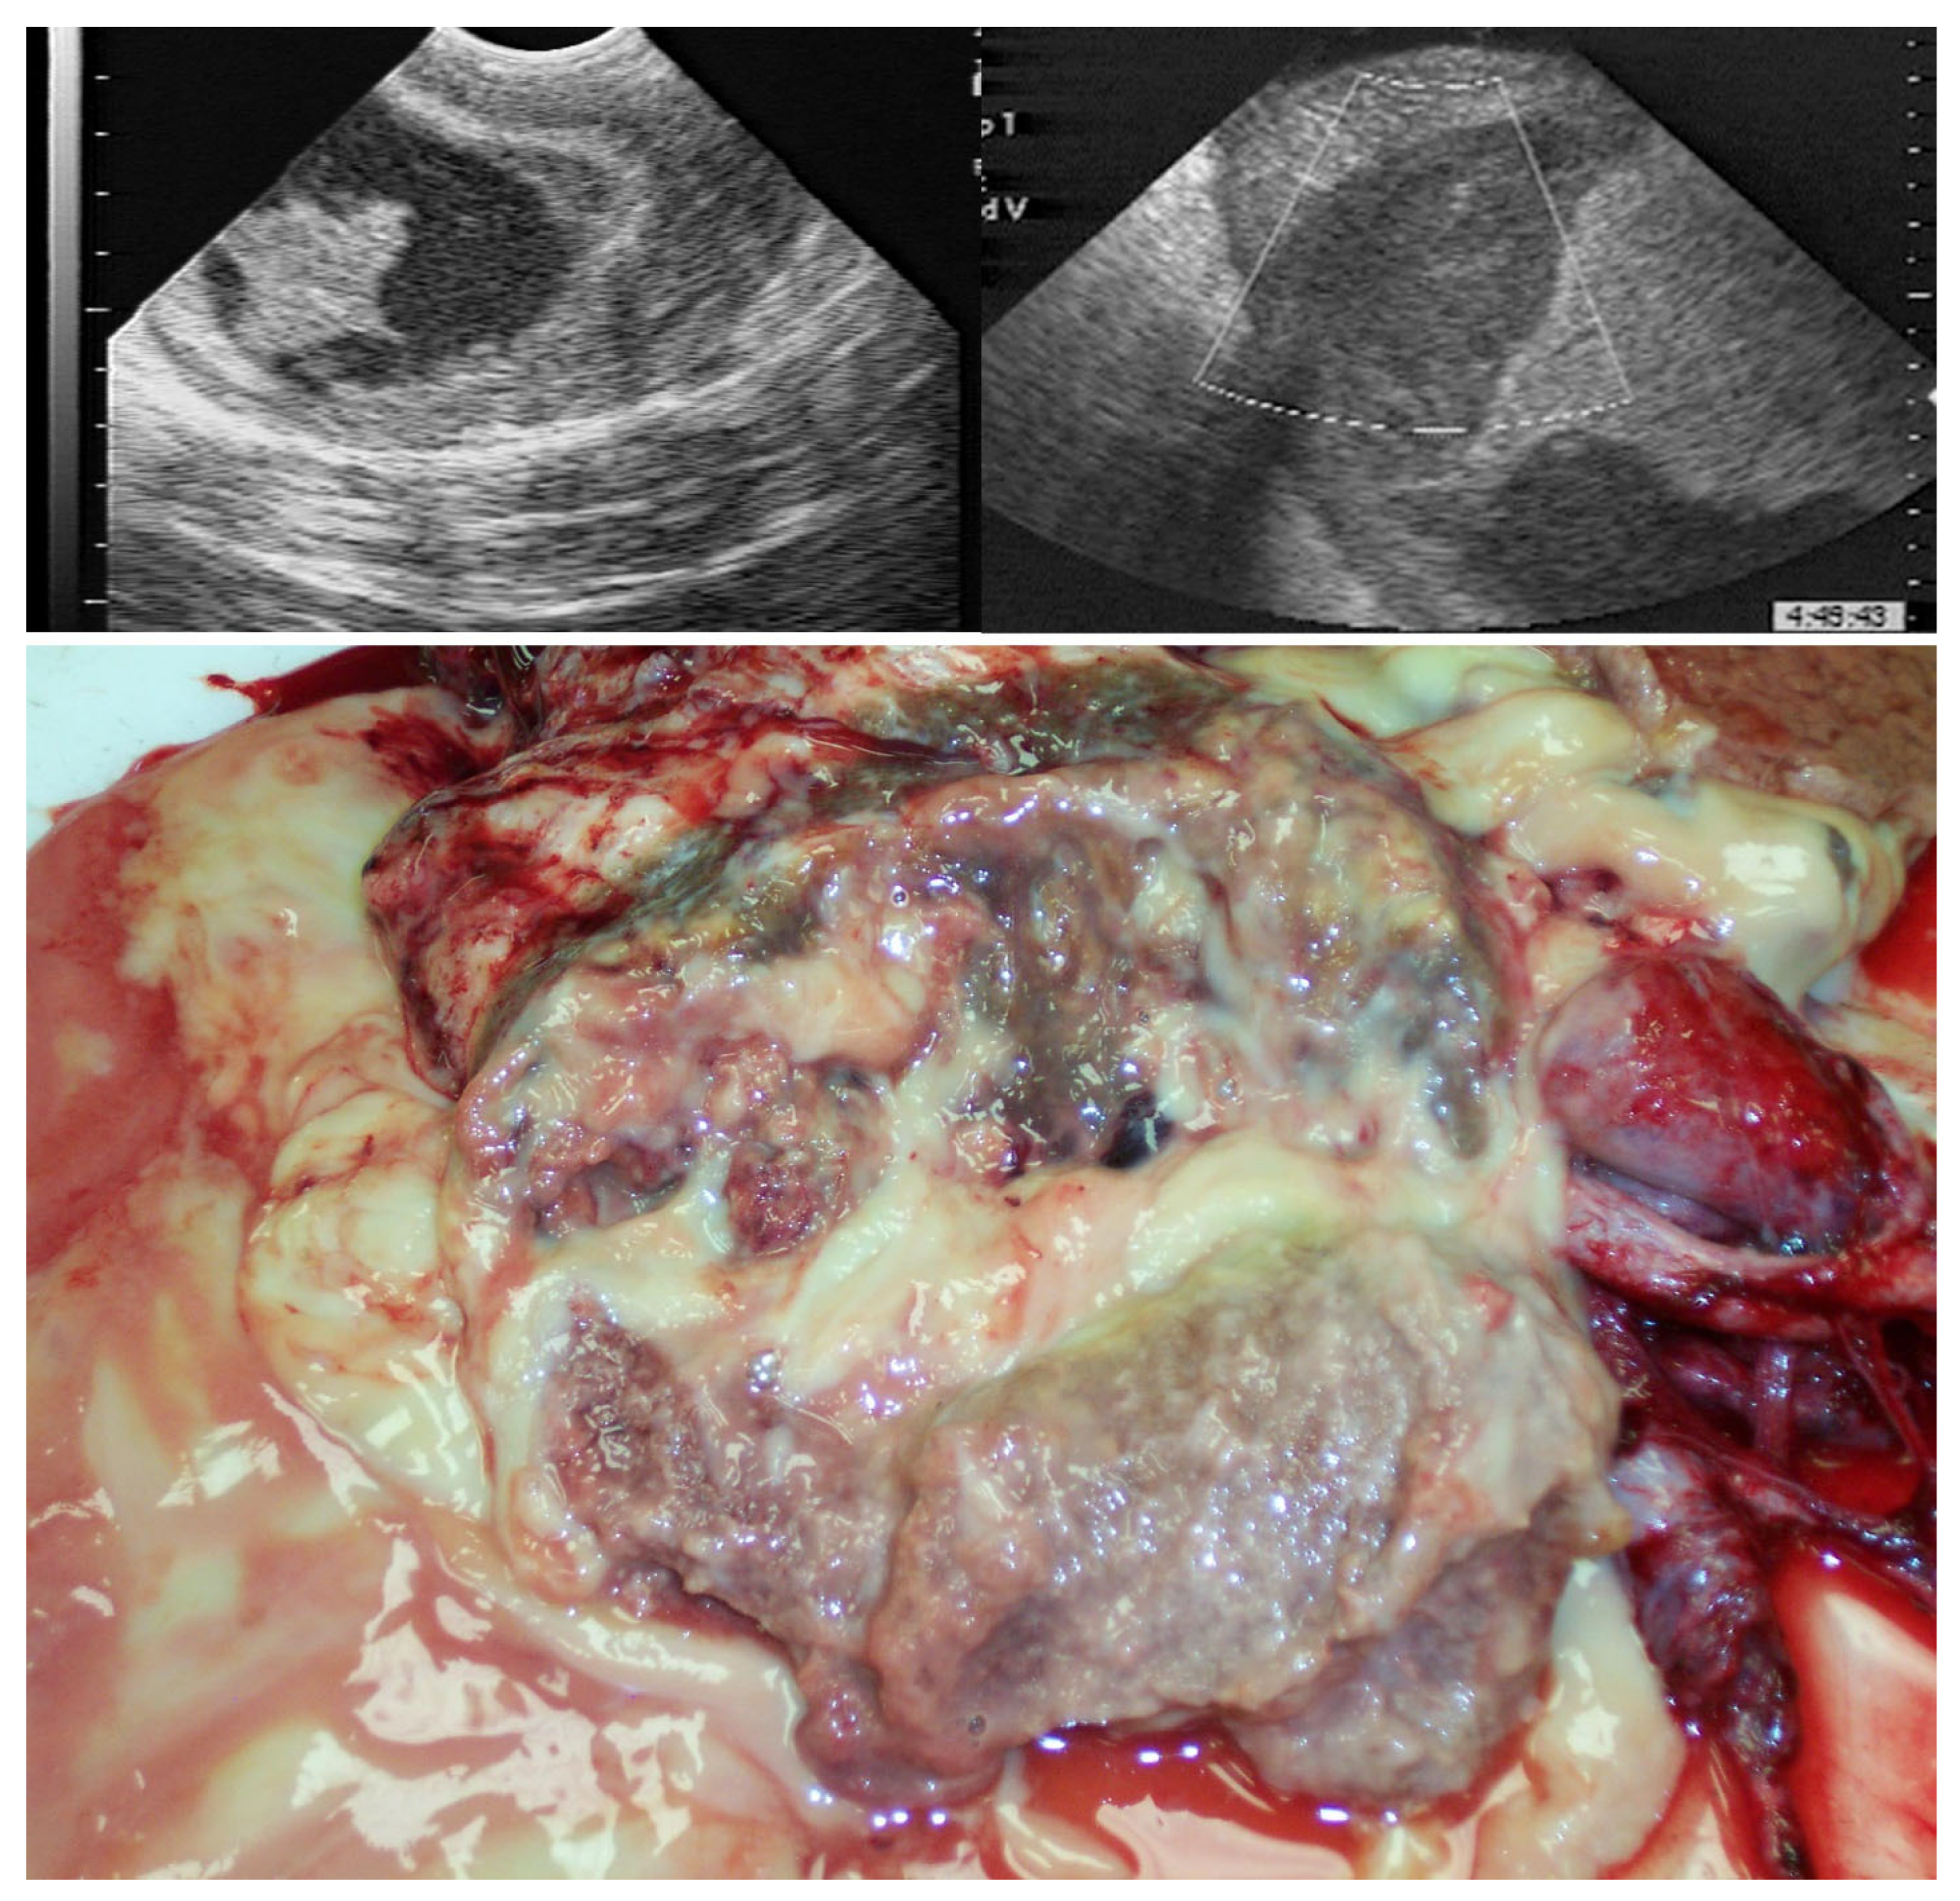

4.2. Acquired Scrotal/Inguinal Hernia

4.3. Torsion of the Spermatic Cord

- François, I.; Lepage, O.M.; Schramme, M.C.; Salciccia, A.; Detilleux, J.; Grulke, S. Clinical Findings, Surgical Techniques, Prognostic Factors for Short-Term Survival and Long-Term Outcome in Horses with Acquired Inguinal Hernias: Ninety-Eight Cases (2005–2020). Vet. Surg. 2024, 53, 468–476. [Google Scholar] [CrossRef] [PubMed]